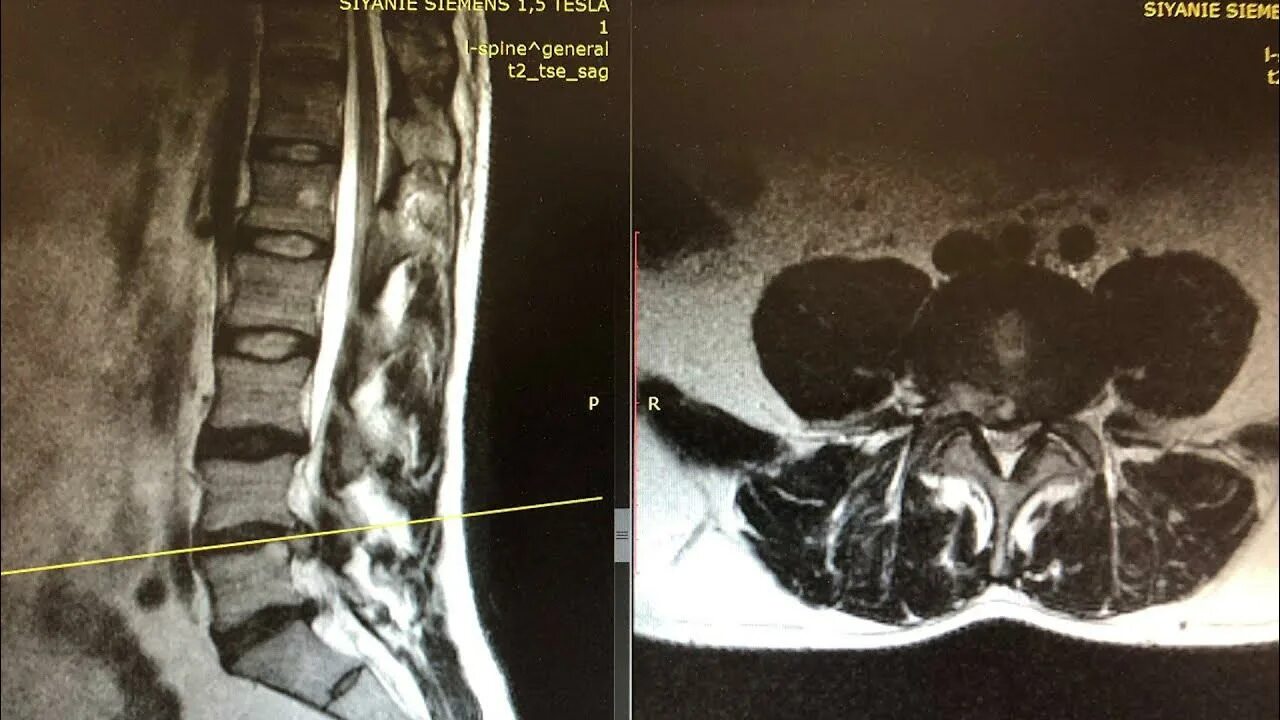

Операция удаление грыжи l5 s1